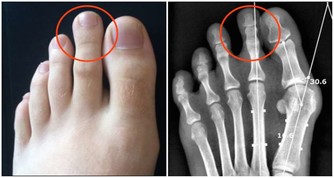

家長要留心孩子的心肺功能,若是發現孩子最近一段時間總是清嗓子,不喜歡外出運動,體力下降了,可能是肺功能降低了,建議進一步到醫院確診。